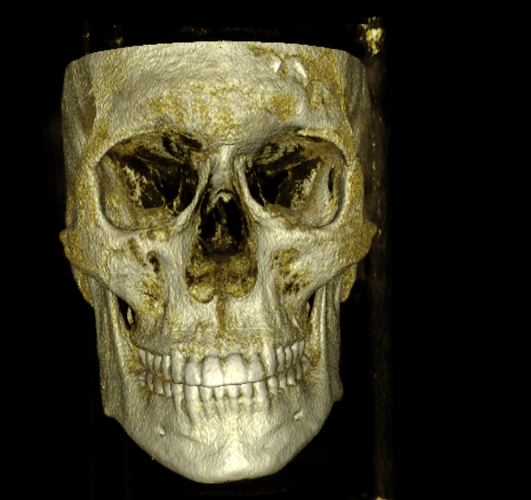

CBCT RENDERS

All attached. Frontal bone, left lateral, right lateral, soft tissue overlays, volume renders at different thresholds. The full skull, nothing hidden, nothing frauded with angles. You can see every problem I just described for yourself.

CBCT RENDERS

All attached. Frontal bone, left lateral, right lateral, soft tissue overlays, volume renders at different thresholds. The full skull, nothing hidden, nothing frauded with angles. You can see every problem I just described for yourself.